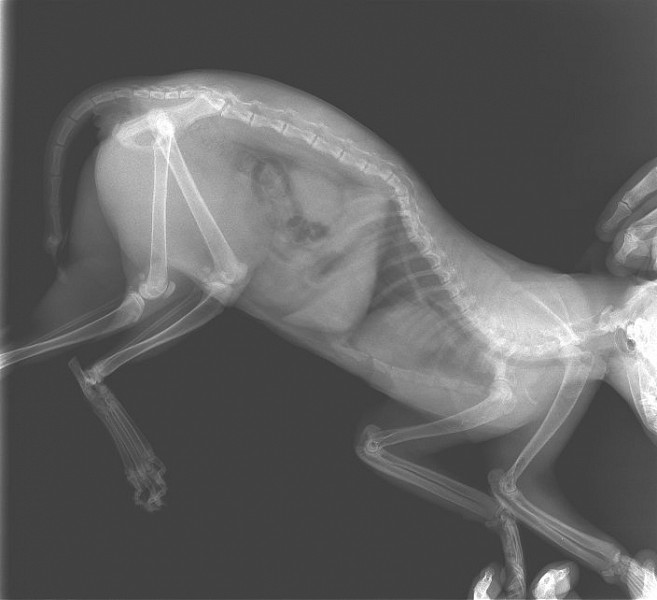

Рентгеновские снимки перелома лапы у кота: диагностика и лечение